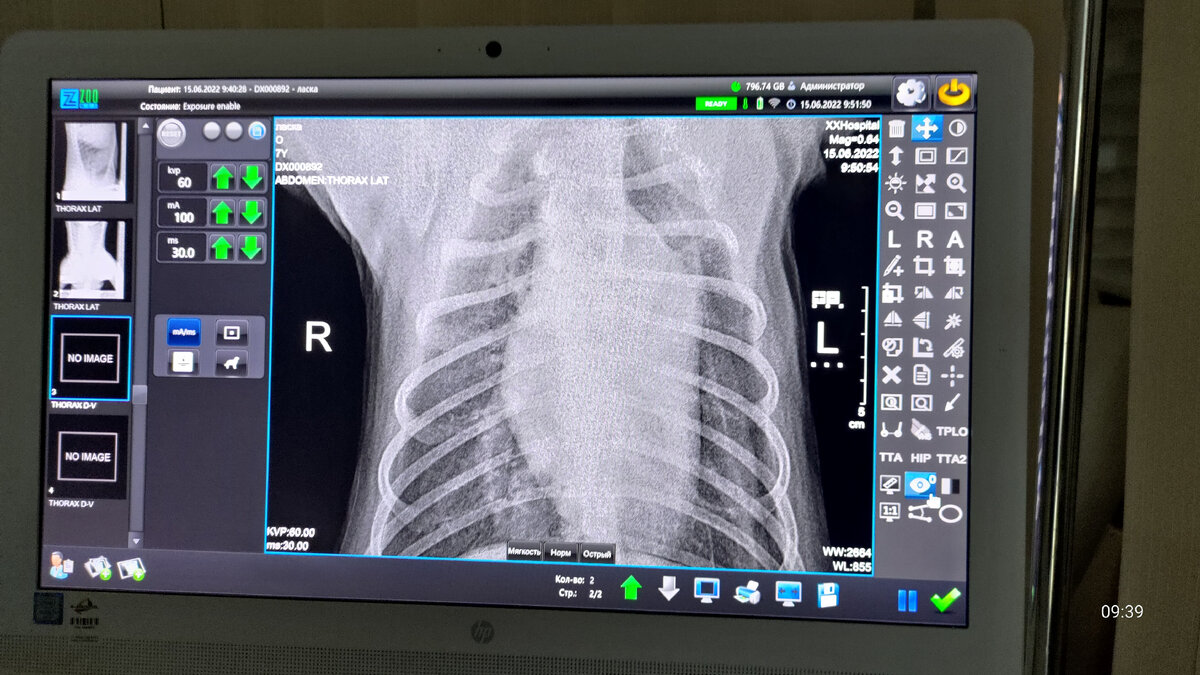

Добрый день друзья, не этот текст я хотел писать сегодня, а про то как съездили в новый макдак, но как всегда жизнь вносит коррективы. Сегодня утром мы поехали на обследование с Лаской, сделали рентген легких, сдали кровь на анализ. Александр (наш вет. врач) осмотрел уплотнение на животе. Резюме следующее. Легкие чистые, но повторный осмотр будет через пару месяцев, но у ласки Диабет, как у Айсан. Сейчас я даю ей такие же лекарства как и хаски Айсан, для печени и почек и конечно инсулин, через пару дней она должна будет выглядеть получше. На данный момент нудно стабилизировать сахар, особенно после недавней течки, а потом будем готовится к операции. По поводу уплотнений сейчас нужно смотреть, как идёт динамика, но в любом случае пока сахар высокий операцию не получится сделать. Так же для после операционного восстановления лучше чтобы собака находилась в прохладном помещении, но с этим как раз проблем не будет, у нас для хаски есть кондиционер. Вот такая среду у нас получилась,

Легкие чистые, но повторный осмотр будет через пару месяцев, но у ласки Диабет, как у Айсан.